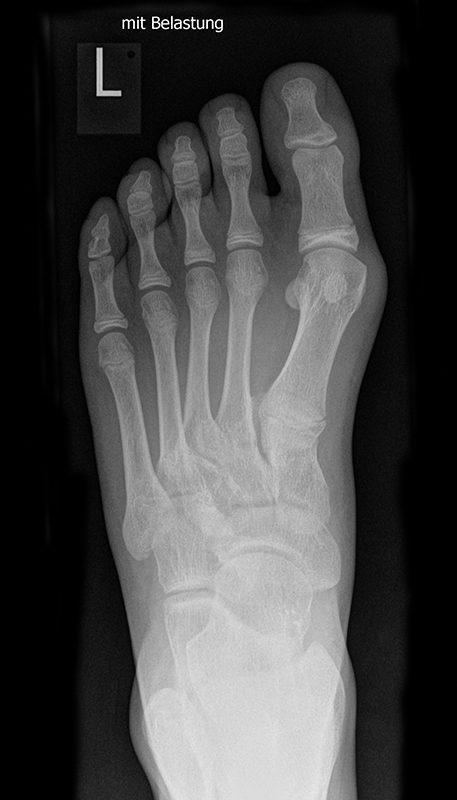

Die folgenden Bilder zeigen die belastete Röntgenaufnahmen des linken Fußes einer jungen Patientin zu Beginn der Therapie und nach 6 Monaten Training. Erkennbar ist die höhere muskuläre Verspannung des Fußes mit verbesserter Stellung der milden Hallux valgus Deformität.

Zum Lesen der Bildbeschreibung und zur Vollansicht bitte die Bilder anklicken.